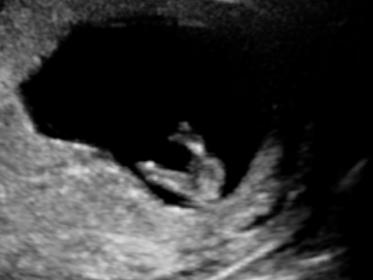

Hi everyone, i have a looong wait til getting comfirmation of gender (20 wk scan, im 14wks today)

Your guesses are appreciated muchly !

Maybe boy

Boy

The angle of dangle points UP and in the crotch shot there shouldn't be anything there! BOY!

Fantastic thanks for the info! Hoping for a boy too!